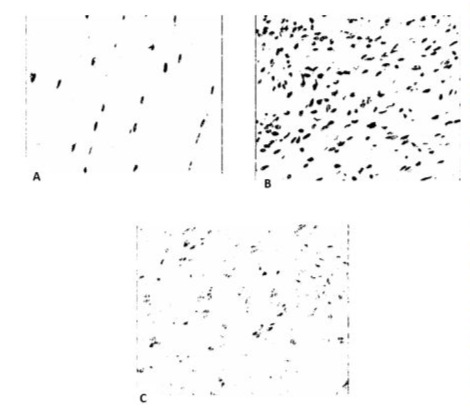

The data were analyzed using the STATA 14.0 program (StataCorp LP, College Station, TX, USA). Tables of central tendency and dispersion measures were used for the descriptive analyses. The normal distribution of the sample was assessed using the Shapiro-Wilk test. The differences in blood vessel counts of the individuals in the three groups were compared using Analysis of Variance (ANOVA) followed by Bonferroni post-hoc analyses. For all tests, a p-value less than or equal to 0.05 was considered significant. After the preparation described above, 14 slides were considered suitable for analysis of the number of blood vessels by the Pathology Department and were allocated to the Sham Group (n=4), Control Group (neuroma without cryotherapy) (n=6) and Cryotherapy Group (n=4). Slides that did not show adequate representation of the area of interest, which allowed histological evaluation, were excluded. There was no statistical impact on the final result of the study. Table 3 shows the blood vessel count values of the different groups. Figure 6 shows the microscopic image of one slide from each group with the blood vessel count, digitized at x200 magnification, using the hot spot principle. Figure 7 shows the difference in the appearance of the neuroma in the Control group and the Cryotherapy group at the end of the study.

Figure 6: Histological evaluation of the number of vessels, scanned at x200 magnification, using the hot spot principle. Slide from the Sham Group, with only 1 vessel (A). Slide from the Control Group, with an increase in the number of vessels (B). Cryotherapy Group (C).